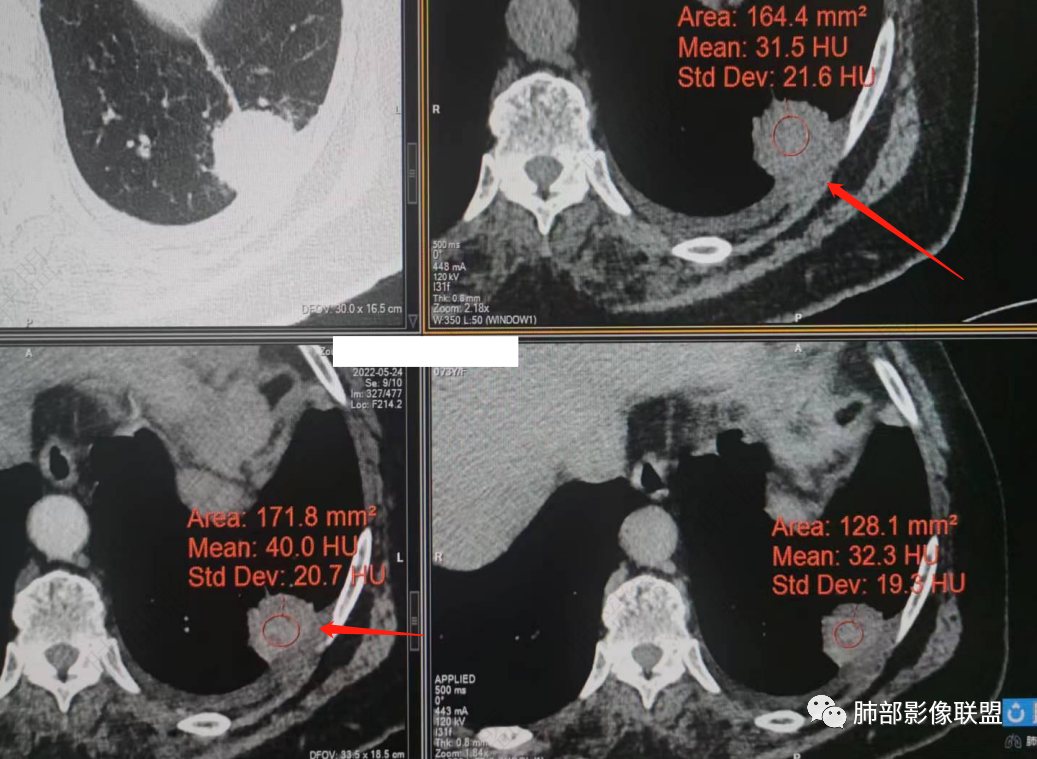

我就不知道这些是胸水,伪影导致密度增高?还是胸膜增厚?

我只是邓较瘦:今天平扫的像栽赃, 增强感觉是增厚的胸膜。

南边:一般这类侵袭,是中央地带毛刷状延伸到胸膜内。

而且旁边这么宽的少,所以觉得很奇怪,不太符合,我是怀疑与照片有关。

你对比一下两侧的密度。肌肉密度不一样。

我只是邓较瘦:南大这个我感觉局部似乎是栽赃呢 箭头那里是啥?

南边:栽赃是这样过去的,中间不会脂肪间隙清晰。

胸壁的组织,除非你怀疑胸壁转移结节。

转移淋巴结。

局部侵犯。有差异。

我只是邓较瘦:这个是侵犯出去不是淋巴结吧?

南边:不是,你看看强化与淋巴结不一致。

我只是邓较瘦:强化与肿瘤差不多。

南边:是。